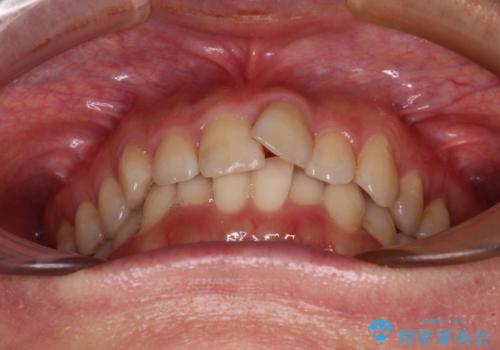

- 上下前歯のデコボコを気にして来院された患者様です。

叢生は軽度で、ワイヤー矯正でもマウスピース矯正でも対応可能な歯列でした。

仕事と小さいお子さんの育児に追われており、インビザラインの自己管理は続ける自信がないとのことで、ワイヤー装置による矯正治療を行うこととしました。